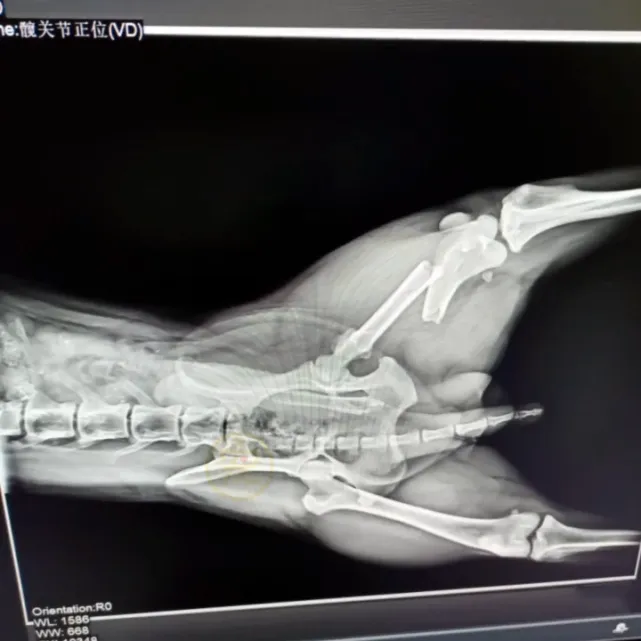

哥哥家距离铲屎官家大约六公里,这个小家伙走了整整七天,中途还因未知原因弄伤了腿,没人知道,这七天它都经历了什么!忠诚的毛孩子却一心只想回家,只想回到主人身边。铲屎官仔细观察了狗狗的腿,发现腿部已经严重变形,一摸狗狗就嗷嗷叫唤,她赶紧带着汪星人去了宠物医院。检查结果表明,狗狗的腿已经骨折并且严重错位,看样子应该是汽车撞击导致的。

可怜的毛孩子,在回家的路上,大概是被车子撞到了,万幸只是撞断了腿,否则铲屎官永远都不会再见到它了。医生为狗狗的腿进行了手术,守在外面的铲屎官既自责又忐忑,如果自己不出去旅游,也许狗狗就不会受伤。

好在手术很成功,只要后续恢复得好,基本不会影响狗狗的正常行走,此时此刻,铲屎官才终于松了一口气。